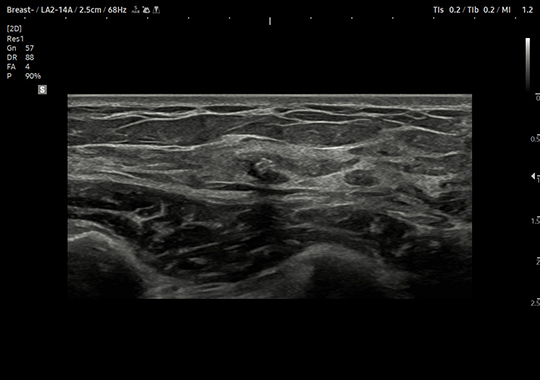

LA2-14A

- Wide Band Linear

- Application: Abdomen, Musculoskeletal, Pediatric, Small Parts, Thoracic, Vascular